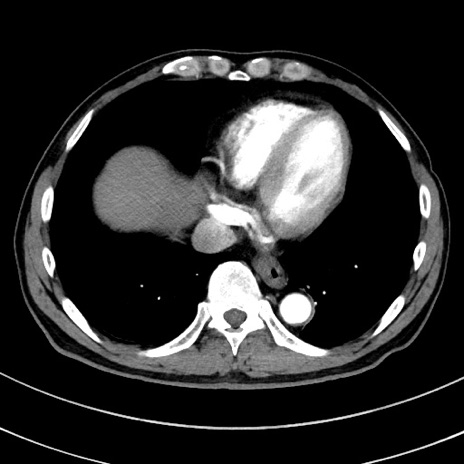

症例8(横断像)

【症例】 60歳代男性

【主訴】 黒色吐物

【現病歴】 4日前から嘔気自覚、2日前の朝食後にも嘔気あり、自分で手で嘔吐反射起こし嘔吐したところ血が混ざっていたため受診。

【既往歴】 5年前汎発性腹膜炎を伴う急性虫垂炎で手術、高血圧、前立腺肥大症、高脂血症

【身体所見】 腹部正中に手術癩痕あり 腹部平坦・軟圧痛なし膨満感あり

【データ】WBC 8400、CRP 4.54